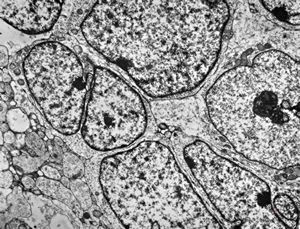

M,55y. | meningotheliomatous meningeoma

M,55y. | meningotheliomatous meningeoma

F,75y. | meningotheliomatous meningeoma